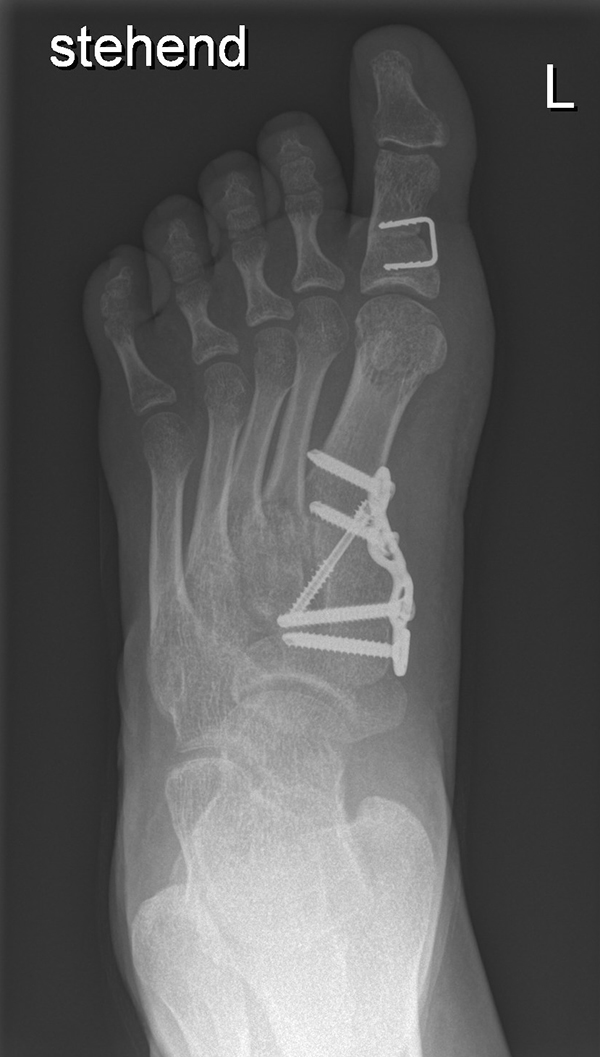

Wachstumslenkung mit moderner Klammer oder eight plate

Bei offenen Wachstumsfugen kann über eine Steuerung des Wachstums mit einer Klammer (Blount-Klammer/Flex Tack) oder kleinen Plättchen (Eight Plate) eine Korrektur von Achsabweichungen in der sagittalen und coronaren Ebene erreicht werden (Abb. 8). Der Hautschnitt beträgt ca. 1,5 - 2 cm und die so versorgten Kinder können ihre Extremität direkt postoperativ schmerzadaptiert voll belasten. Die wachstumslenkende Operation mit einer Klammer oder einem Plättchen besitzt ein enormes Korrekturpotential und erspart dem Kind oder Jugendlichen umfangreiche Umstellungsosteotomien und Plattenosteosynthesen, welche eine Schnittlänge von 15 cm und eine Entlastung des operierten Beines von 4-6 Wochen erforderlich machen.

Abb. 8 a-g: Genua vara prä- und postoperativ versorgt mit Flex Tacks (a-b) und ein Genu valgum versorgt mit Eight Plate an der medialen Femurkondyle (c); Spitzfuß bei congenitalem Klumpfuß und einem Flat Top Talus mit präoperativem Röntgenbild seitlich und der deutlich nach dorsal stehender Tibia(d); intraoperative Bilder der Epiphysiodese mittels Eight Plate zur Wachstumslenkung der distalen Tibia in die Extension (e-f) und postoperativer Verlauf nach sechs Monaten mit regelrecht stehender Tibia über dem Talus durch die distale Extension (g).